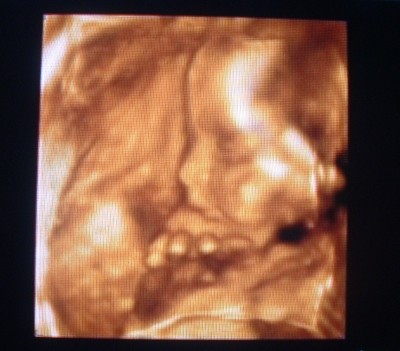

Nagyon csini vagy! Okos párom idejött mögém, s pont a delfines képnél megkérdezte (a képernyőn Cas kisánya, s a delfin látszott csak

): "ő kié?" - most ezen jót mulattam